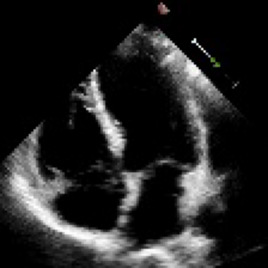

Accurate and consistent predictions of echocardiography parameters are important for cardiovascular diagnosis and treatment. In particular, segmentations of the left ventricle can be used to derive ventricular volume, ejection fraction (EF) and other relevant measurements. In this paper we propose a new automated method called EchoGraphs for predicting ejection fraction and segmenting the left ventricle by detecting anatomical keypoints. Models for direct coordinate regression based on Graph Convolutional Networks (GCNs) are used to detect the keypoints. GCNs can learn to represent the cardiac shape based on local appearance of each keypoint, as well as global spatial and temporal structures of all keypoints combined. We evaluate our EchoGraphs model on the EchoNet benchmark dataset. Compared to semantic segmentation, GCNs show accurate segmentation and improvements in robustness and inference runtime. EF is computed simultaneously to segmentations and our method also obtains state-of-the-art ejection fraction estimation. Source code is available online: https://github.com/guybenyosef/EchoGraphs.

翻译:对回声心电图参数的准确和一致预测对于心血管诊断和治疗十分重要,特别是左心室的分块可用于产生心血管体积、弹出分数(EF)和其他相关测量结果。在本文件中,我们提出一种新的自动化方法,称为EchoGraphs,用于预测弹出分数,并通过探测解剖关键点对左心室进行分解。根据图表变异网络(GCNs)进行直接协调回归模型用于检测关键点。GCNs可以学习根据每个关键点的局部外观以及所有关键点的全球空间和时间结构来代表心脏形状。我们在EchoNet基准数据集上对EchoGraphs模型进行了评估。与语系分化相比,GCNs显示了准确的分化和稳健度和推断运行时间的改进。EF是同时计算分解的,我们的方法也获得了最新化的弹射分数估计。源代码可在线查阅:https://github.com/guybenyos/Echophophs。